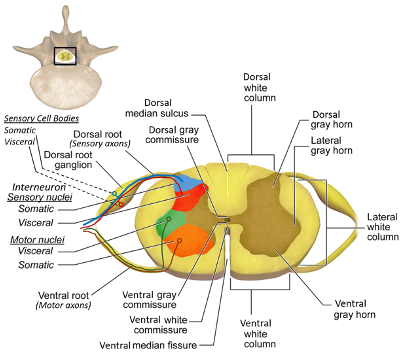

Spinal cross section (1)

Spinal cross section (2)

dorsal horn of spinal cord

cell bodies synapsed by afferent neurons (sensory)

ventral horn of spinal cord

The upper motor neurons that control the skeletal muscles are found in

lateral horn of spinal cord

Contains the cell bodies of the preganglionic ANS neurons

dorsal column

a white matter tract on the dorsal side of the spinal cord, carrying fine touch and proprioceptive axons to the brain stem

spinothalamic tract

pain and temperature

corticospinal tract

What tract is responsible for voluntary refined movements of distal extremities?

dorsal rootlets

ventral rootlets

spinal nerves

central canal of spinal cord

ventral white comissure

Dorsal Root Ganglion (DRG)

associated with the dorsal horns; cell bodies of sensory neurons are located here